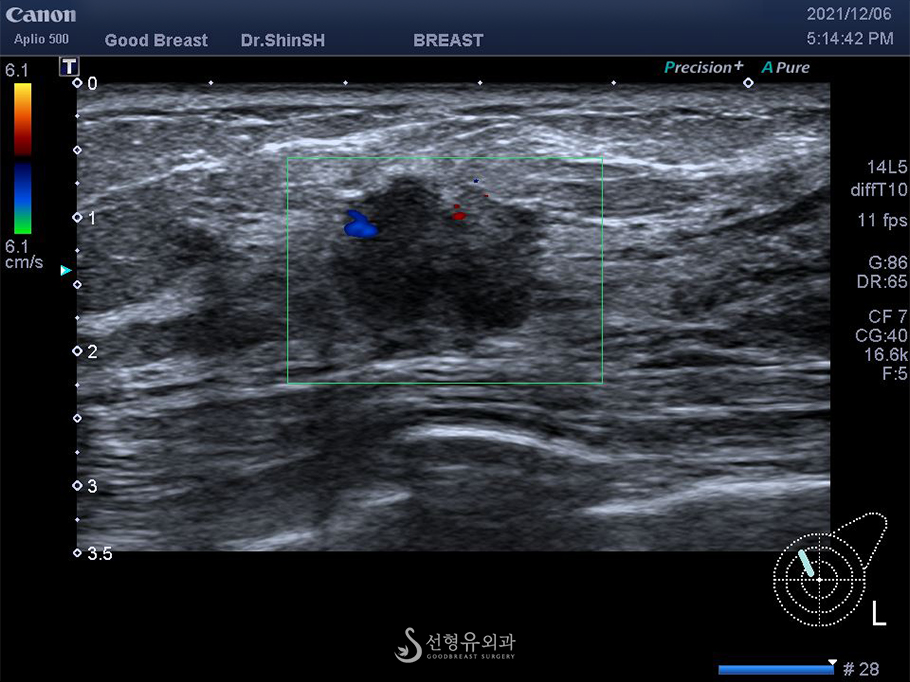

과거에는 초음파 영상으로 혹의 크기와 모양 정도만 확인하였지만 최신 초음파 기계장치는 여러 기능이 탑재되어 단단한 정도와 미세석회병변까지 찾아낼 수 있습니다.